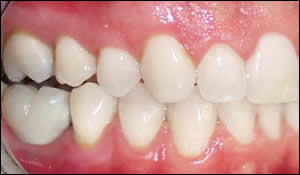

Fig 6: An intraoral view of the implant crown subsequent to whitening the other teeth.